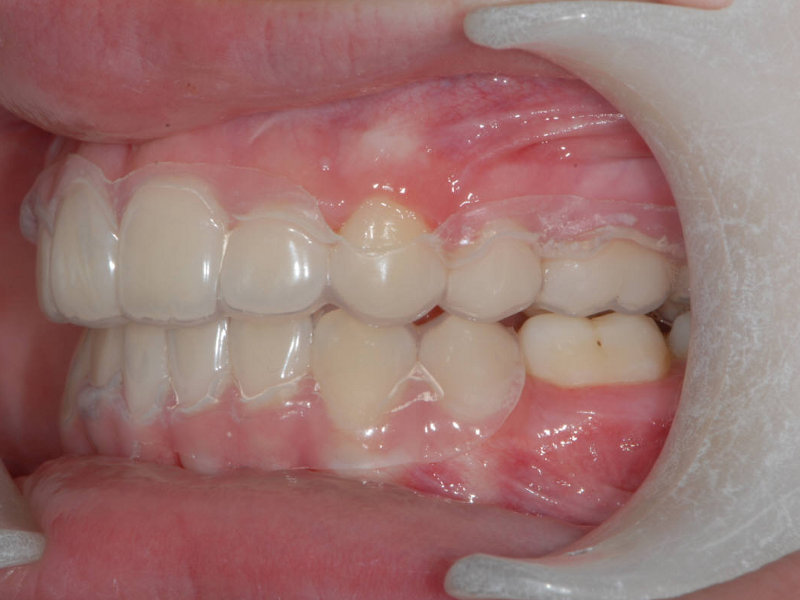

Essixskena (C)